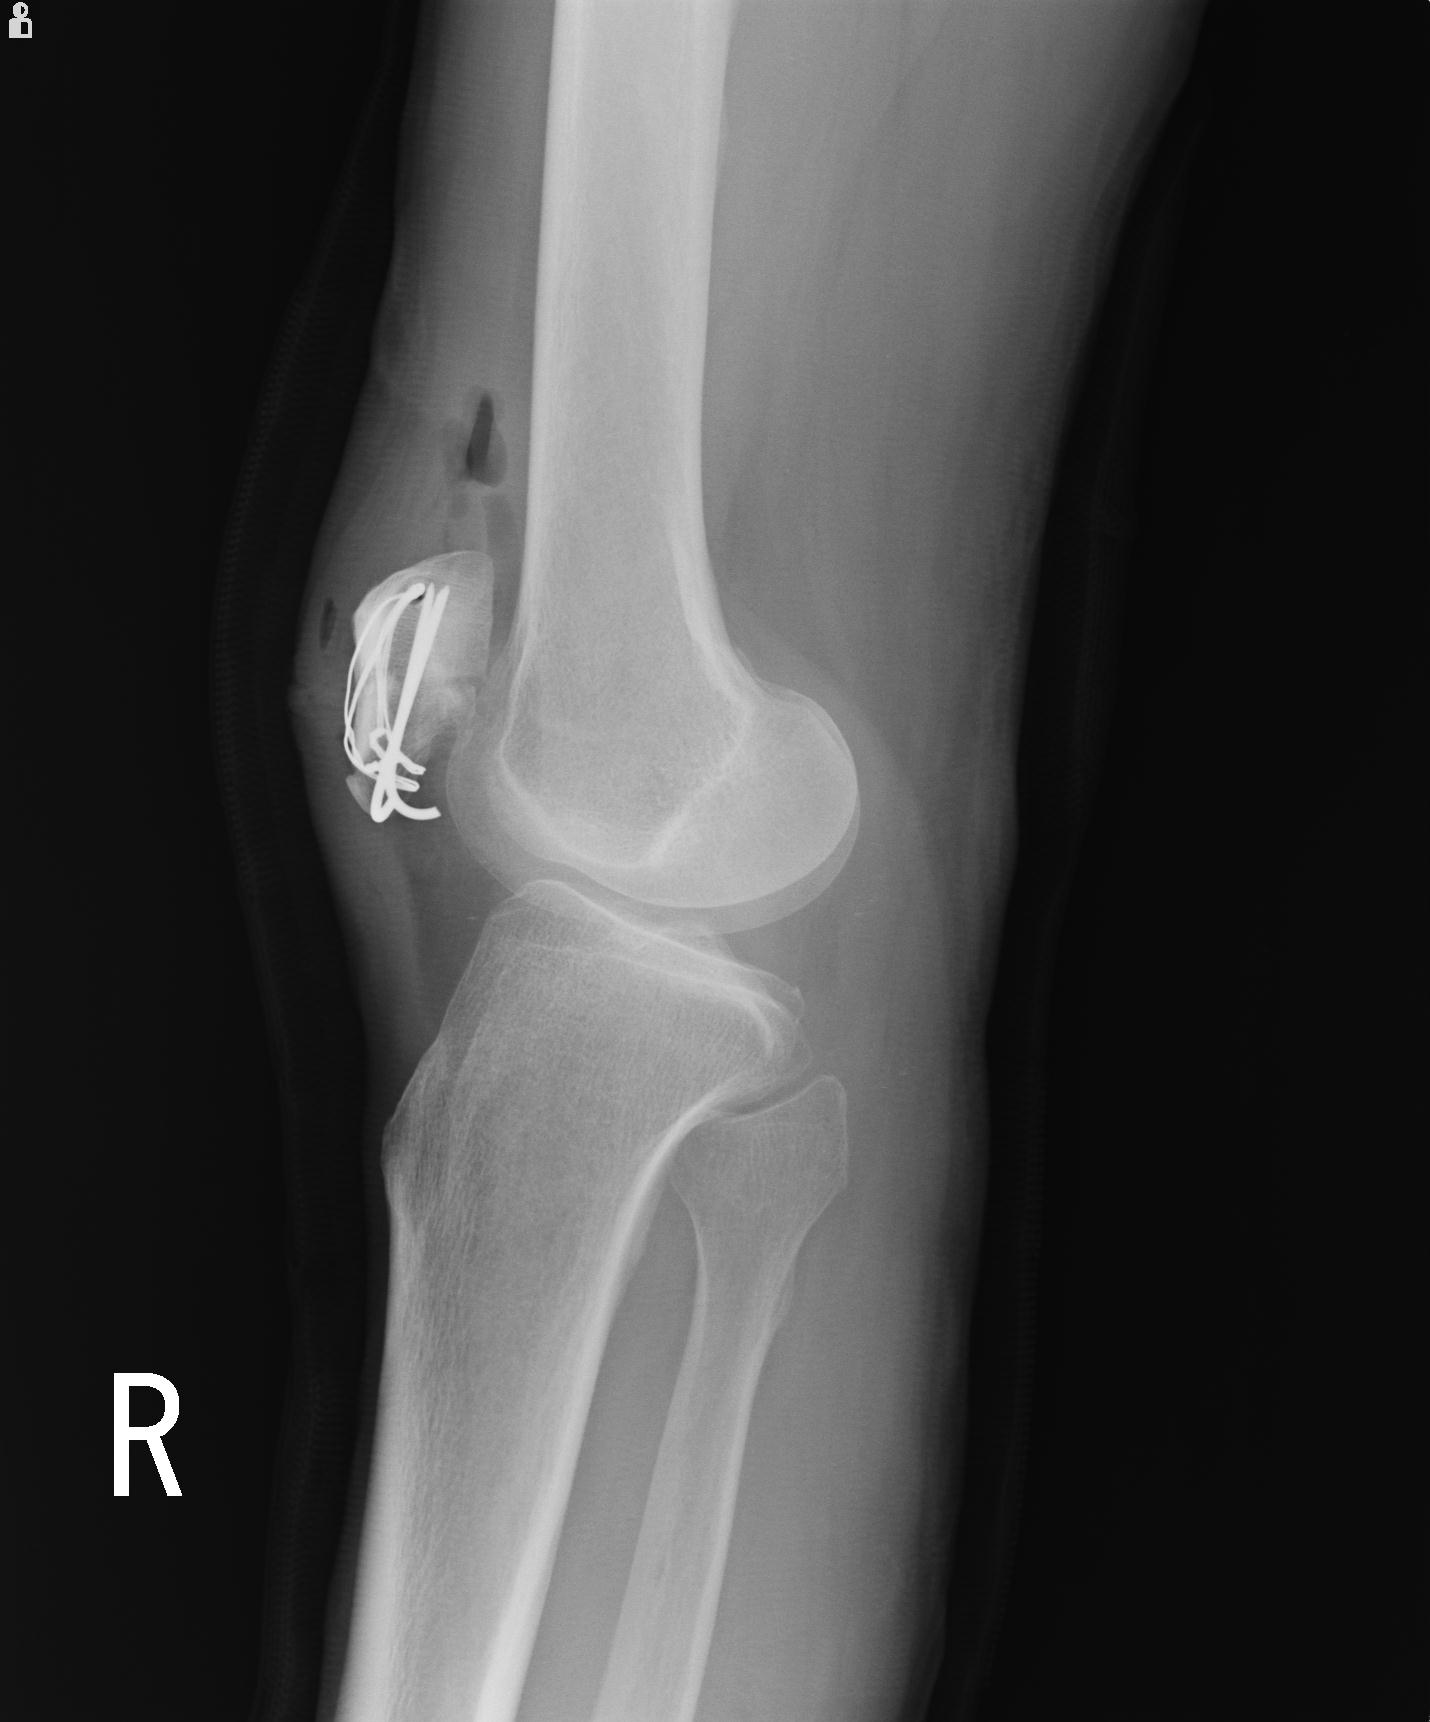

49554 3/13 膝 4R 3/16 4R 1/18 2R 78歳男性 膝蓋骨骨折